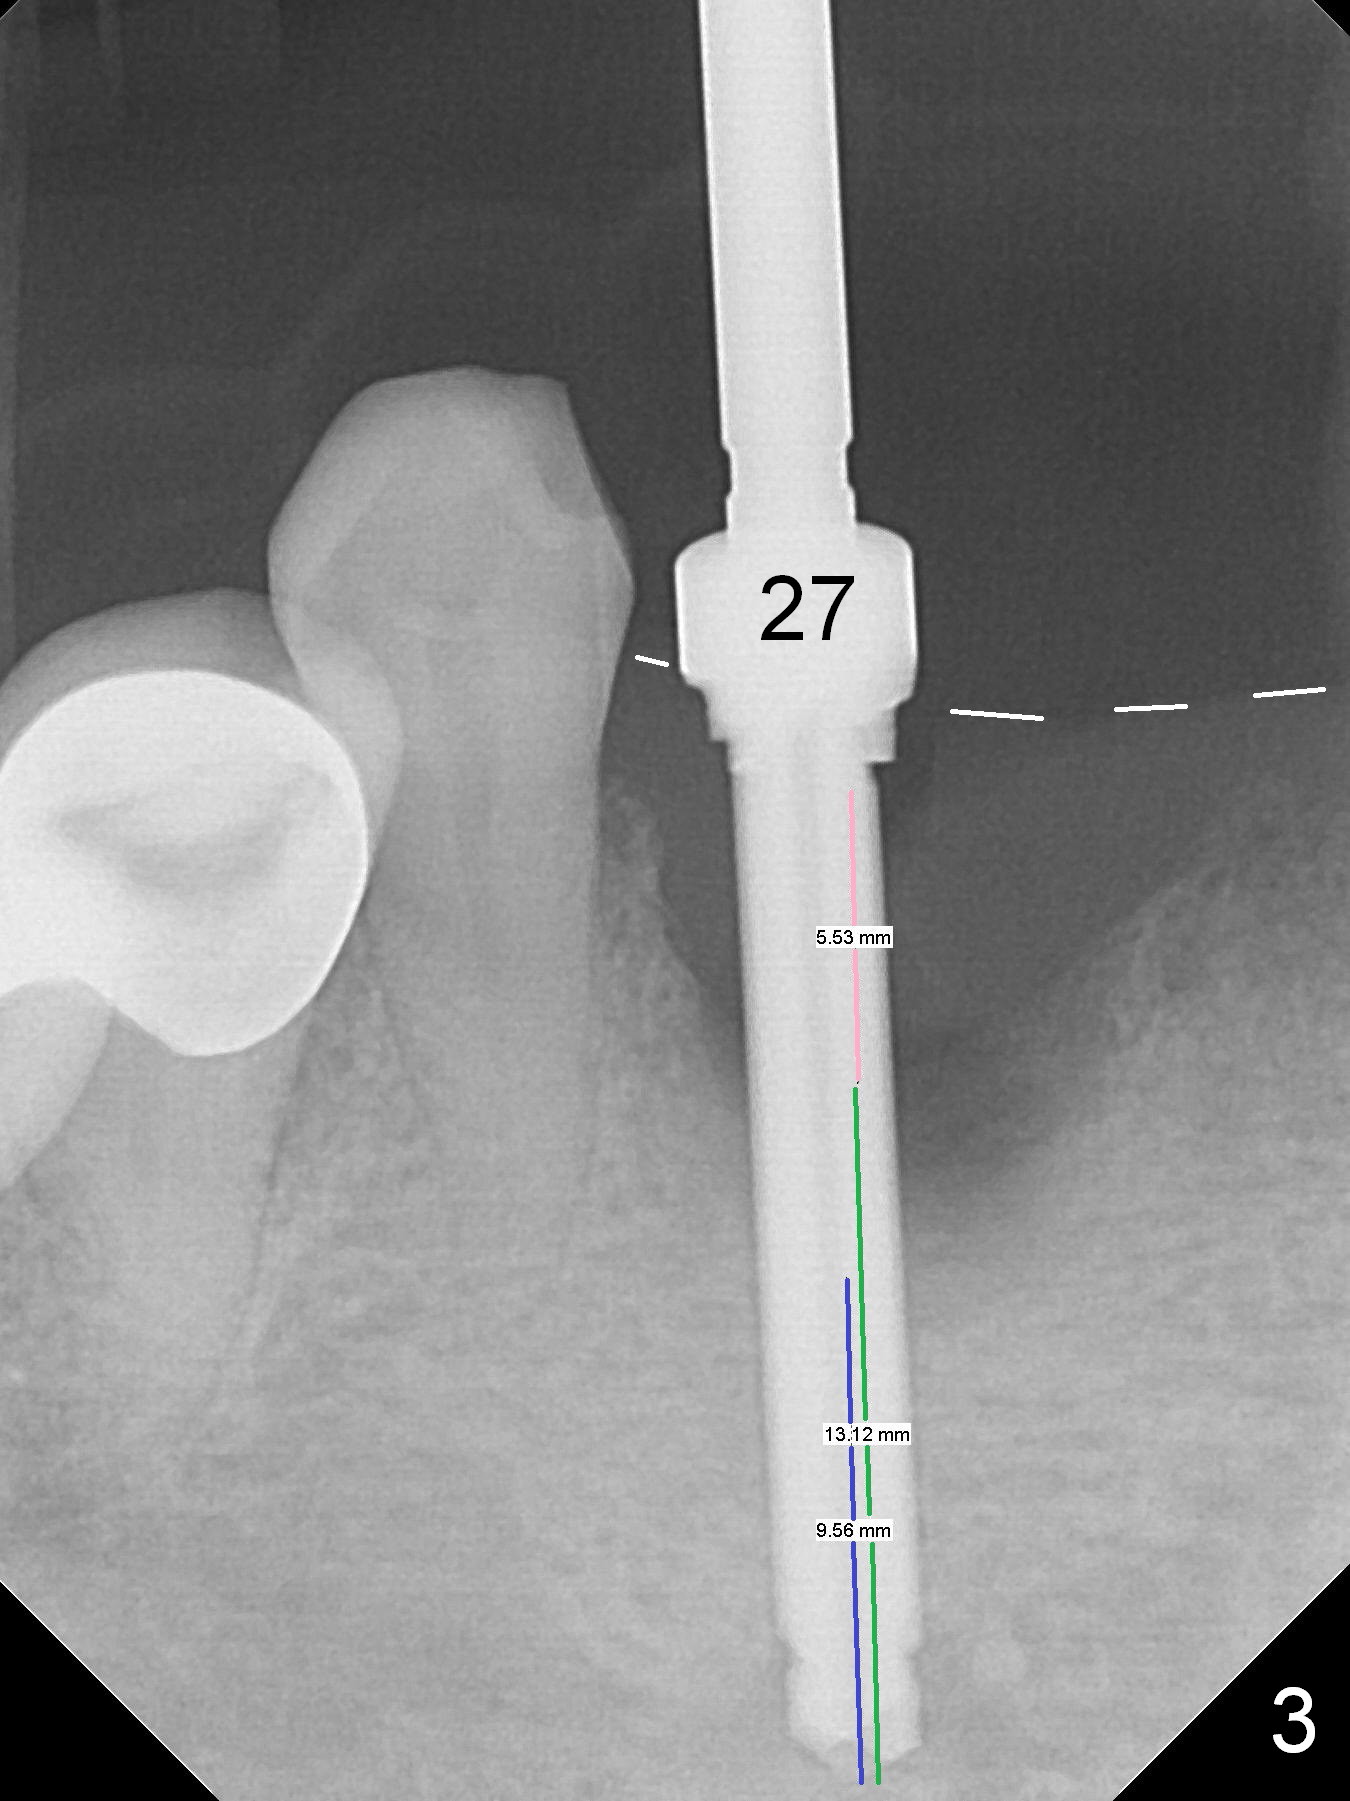

There is severe buccal gingival recession at #27 (Fig.1 arrow), as compared to that at #22. After removing the bridge and extraction of #27 (Fig.2 with severe loss of the buccal plate), a 3x18 mm drill is used to finish osteotomy (Fig.3). A 3.8x13 mm UF implant (Fig.3 green line) will be placed with 9 mm in the apparently solid, native (new) bone (blue line), while the coronal 5 mm will be occupied by the 5 mm cuff of a cemented abutment (pink line). The white dashed line is the gingival margin. The osteotomy is initiated as lingual as possible so that there will be at least 2 mm buccal gap when the narrow implant is placed. In spite of effort and precaution (guided surgery could control the trajetory), the coronal end of the implant tilts buccally so that a 4.5 mm 15 ° A 4 mm angled abutment is placed slightly subgingival (except buccal; Fig.5 A).